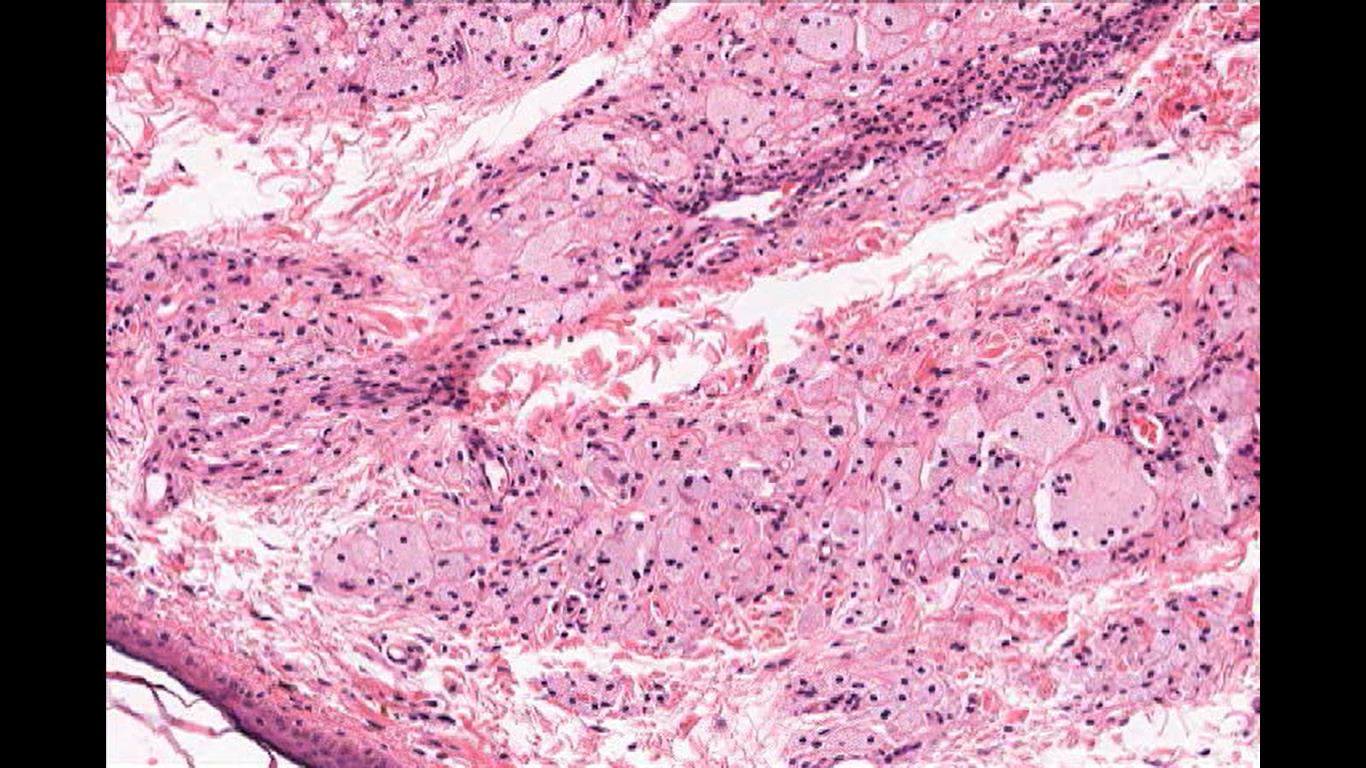

The classic presentation of ocular involvement of ECD is of bilateral proptosis caused by infiltrating orbital masses, especially in the setting of associated periorbital xanthelasma. Proptosis can be severe and result in painless ophthalmoplegia and decreased visual acuity from diffuse intraconal orbital infiltration causing compressive optic neuropathy. In addition to proptosis, other ophthalmic manifestation of ECD include, xanthelasma of the eyelids (image 2), eyelid thinning, bullous chemosis, decreased visual acuity from exposure keratopathy and periorbital edema. Ophthalmic examination can reveal optic disc edema or atrophy and retinal striae from compression, bilateral lacrimal gland enlargement, and extension of mass lesions beyond the orbital apex and skull base into the intracranial space invading the cavernous sinus with multiple cranial nerve deficits and rarely extending further to the pituitary gland and optic chiasm. While vision loss in cases of orbital ECD occurs most commonly secondary to orbital or anterior visual pathway compression of the optic nerves, involvement of the central nervous system by masses affecting the posterior visual pathways have resulted in homonymous hemianopia.

Image 2: Xanthelasma Cells, cutaneous manifestation of lipid laden foamy cells in the epidermis. They manifest as yellowish white plaque like lesions in the eyelid skin, commonly in the medial canthus. Image courtesy of Dr. William Morris, M.D.